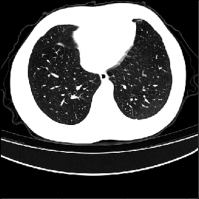

Recent studies indicate that detecting radiographic patterns on CT scans can yield high sensitivity and specificity for COVID-19 localization. In this paper, we investigate the appropriateness of deep learning models transferability, for semantic segmentation of pneumonia-infected areas in CT images. Transfer learning allows for the fast initialization/ reutilization of detection models, given that large volumes of training are not available. Our work explores the efficacy of using pre-trained U-Net architectures, on a specific CT data set, for identifying Covid-19 side-effects over images from different datasets. Experimental results indicate improvement in the segmentation accuracy of identifying COVID-19 infected regions.